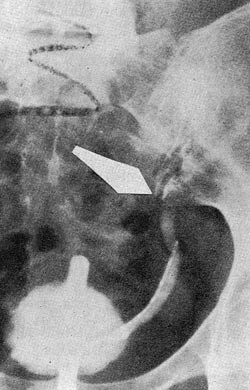

Urin: sp.v. 1012, protein+, Esbach 0,2 , Guajak-. Mikroskopi: Tallrike leukocytter, staver og kokker i korte kjeder og diploform. TB-. Rest-N 50 mg/100 ml. Urografi: Høyre nyreskygge mangler. Venstre nyreskygge noe stor. Noe forsinket utskillelse idet det 7 minutter etter injeksjon av 20 ml Nycotrast bare er antydning til kontrast i enkelte calyces, etter 30 minutter god fylling. Nyrebekkenet noe utvidet med plumpe calyces. Ureter dilatert, ca. 1 cm bred helt ned til blæren, men området foran sacrum kommer ikke fram på grunn av svak kontrastskygge. Dårlig fylling av blæren etter 1/2 time. R: «Manglende høyre nyre. Hydronephrosis sin. Nedsatt nyrefunksjon» (B. Medby) (fig. 1). Cystoskopi viste et rundt og litt trangt venstre ureterositum, ved kromoskopi kom svak blåfarge i repriser etter 35 minutter. Ureterkateteret gikk 11cm opp, selv det tynneste kateter lot seg ikke føre lenger opp.

Ved retrograd ureterografi lot det seg ikke gjøre å presse kontrast lenger opp enn nedre kant av venstre iliosakralledd. R: «Hindret passasje i venstre ureter» (fig. 2).